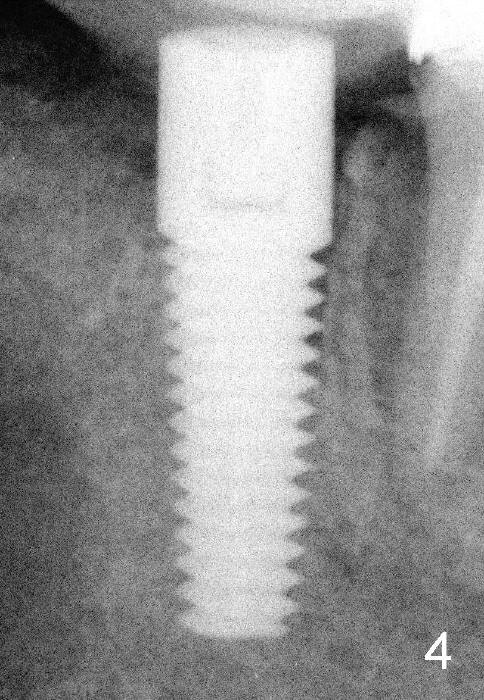

Three and a half months postop, the bone grows into the threads of the implant (Fig.5 <, as compared to the same area of Fig.3,4 (immediately postop).